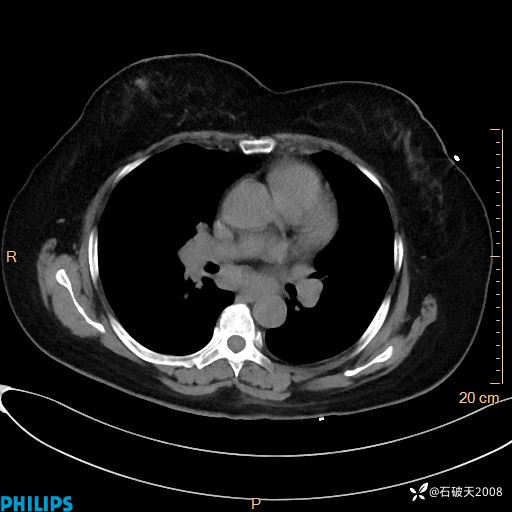

肺窗

纵隔窗